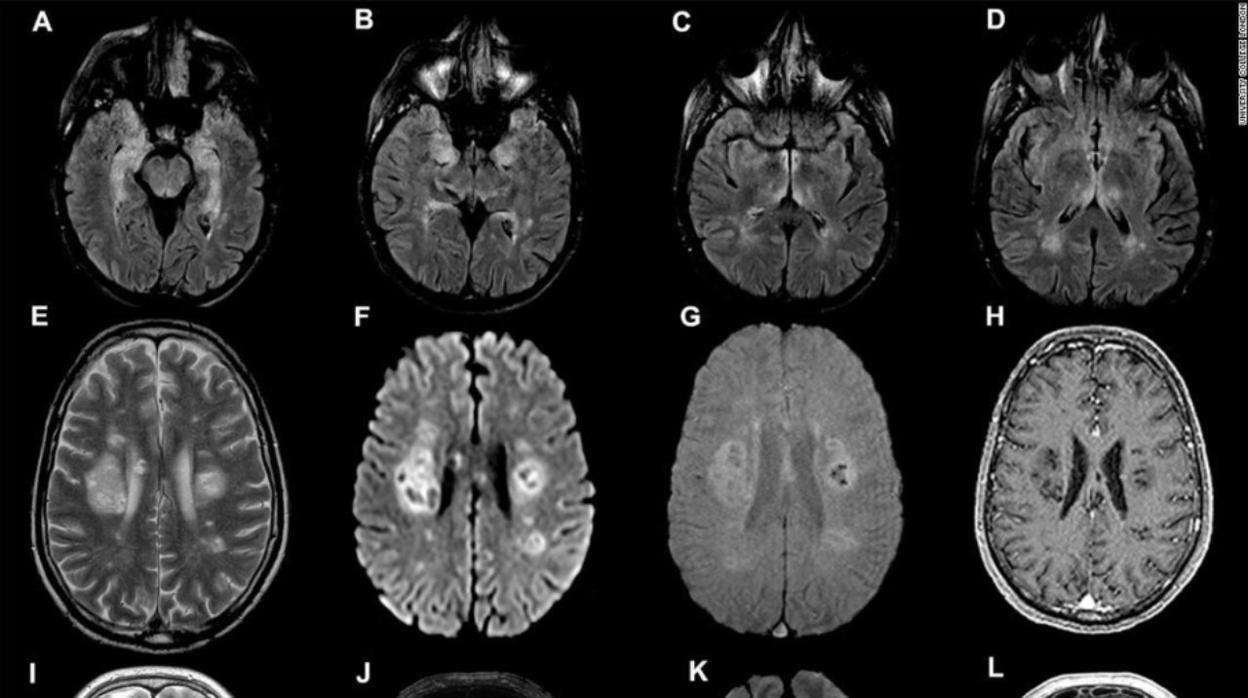

Varios escaneos cerebrales de distintas patologías en un estudio publicado en julio University College of London / Vídeo: El coronavirus puede provocar un mal funcionamiento del cerebro

Por ejemplo, se ha descrito la pérdida del gusto y del olfato, ictus o encefalitis . Algunos pacientes sufren confusión, delirios o nauseas y encuentran difícil concentrarse. Ahora, un estudio publicado en « Seizure: European Journal of Epilepsy », ha recopilado decenas de investigaciones sobre cómo el virus afecta al cerebro, y cuyos efectos se pueden medir por medio de electroencefalografía (EEG), una técnica que registra la actividad eléctrica de varias partes del cerebro, por medio de una serie de electrodos fijados en el cráneo.

Los electroencefalogramas mostraron un amplio espectro de anormalidades en el cerebro, como patrones rítmicos de actividad que recuerdan a los que se manifiestan en pesonas epilépticas. La anormalidad más común fue un ralentizamiento de las ondas cerebrales, que se suele asociar con un mal funcionamiento general del cerebro.

Los investigadores creen que en el caso de la COVID-19 este mal funcionamiento general puede producirse como resultado de una inflamación extensa del cerebro , o como consecuencia de una caída del riego sanguíneo, a causa del debilitamiento de los pulmones y del corazón.

Una tercera parte de las anormalidades registradas se encontró en el lóbulo frontal, la parte del cerebro encargada de tareas ejecutivas, como el razonamiento lógico y la toma de decisones . Este lóbulo frontal también regula las emociones y el comportamiento y está implicado en el aprendizaje y la atención.